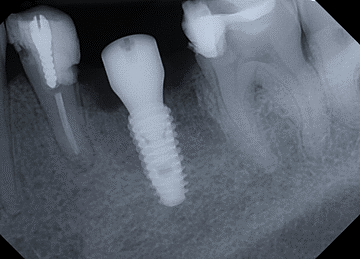

Tooth 4.8 is planned for extraction. Which radiographic findings suggest an increase in the degree of difficulty of the extraction?

13. (Select ONE OR MORE correct answers.)

Tooth 1.8 is planned for surgical extraction. Which radiographic findings suggest an increase in the degree of difficulty of the extraction?

Tooth 2.8 is planned for surgical extraction. Which radiographic findings suggest an increase in the degree of difficulty of the extraction?